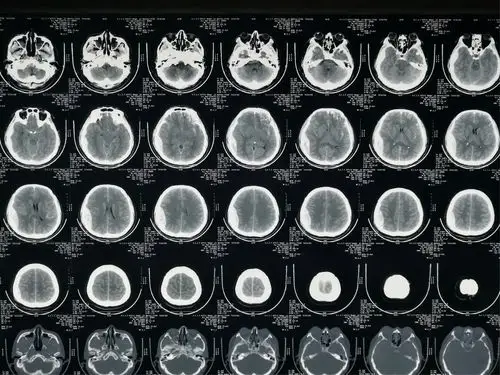

必点收藏颅内疝影像汇总

钟书教授专栏丨中枢重症第26期图解脑疝

各种疝的ct影像诊断

脑疝后ct